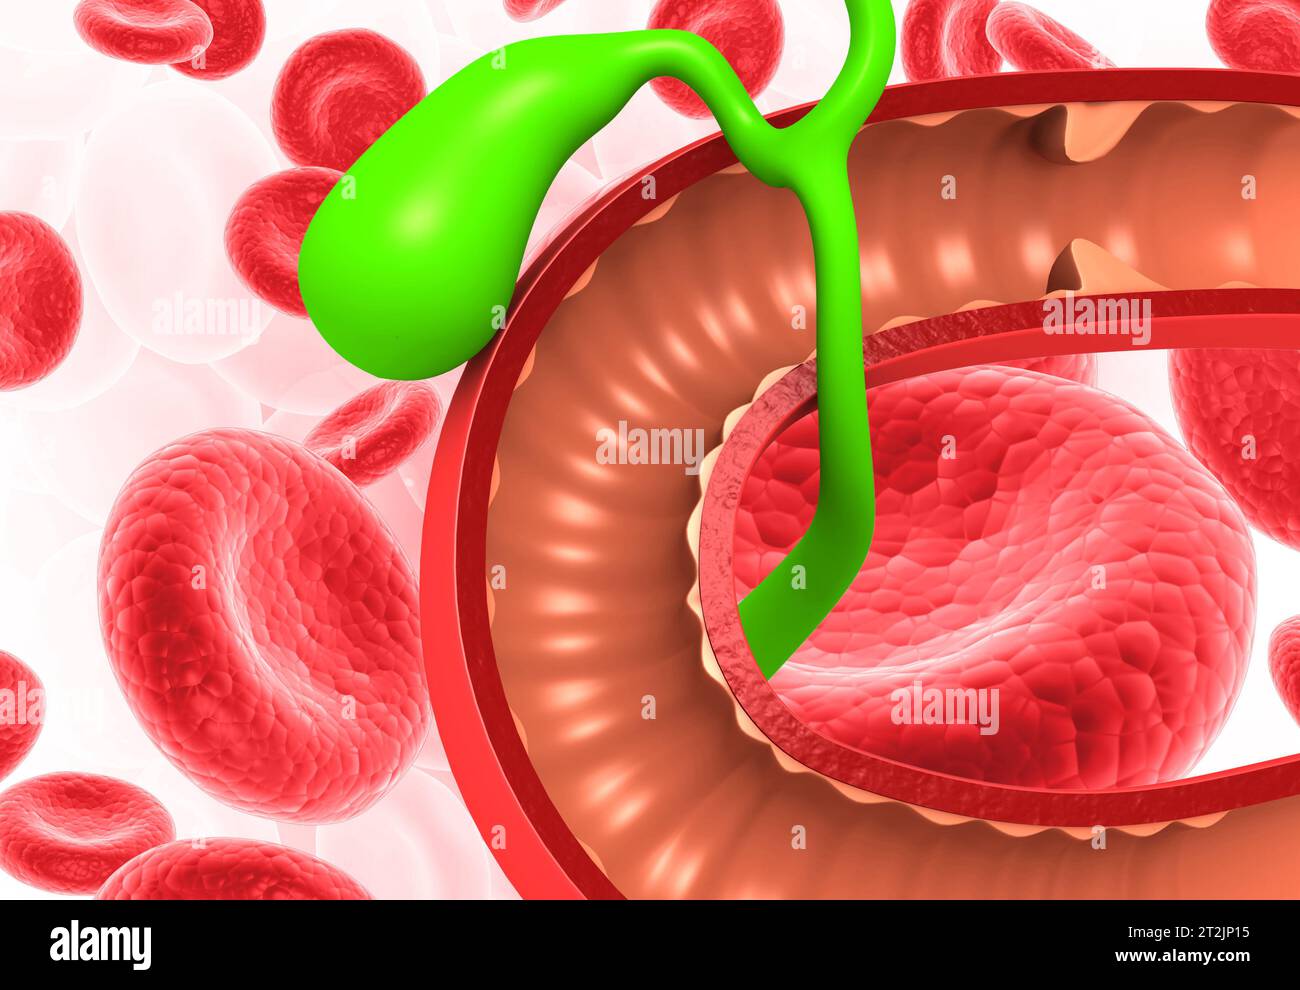

Anatomie de la vésicule biliaire hépatique avec globules rouges. rendu 3d. Banque D'Imageshttps://www.alamyimages.fr/image-license-details/?v=1https://www.alamyimages.fr/anatomie-de-la-vesicule-biliaire-hepatique-avec-globules-rouges-rendu-3d-image569583873.html

Anatomie de la vésicule biliaire hépatique avec globules rouges. rendu 3d. Banque D'Imageshttps://www.alamyimages.fr/image-license-details/?v=1https://www.alamyimages.fr/anatomie-de-la-vesicule-biliaire-hepatique-avec-globules-rouges-rendu-3d-image569583873.htmlRF2T2JP15–Anatomie de la vésicule biliaire hépatique avec globules rouges. rendu 3d.